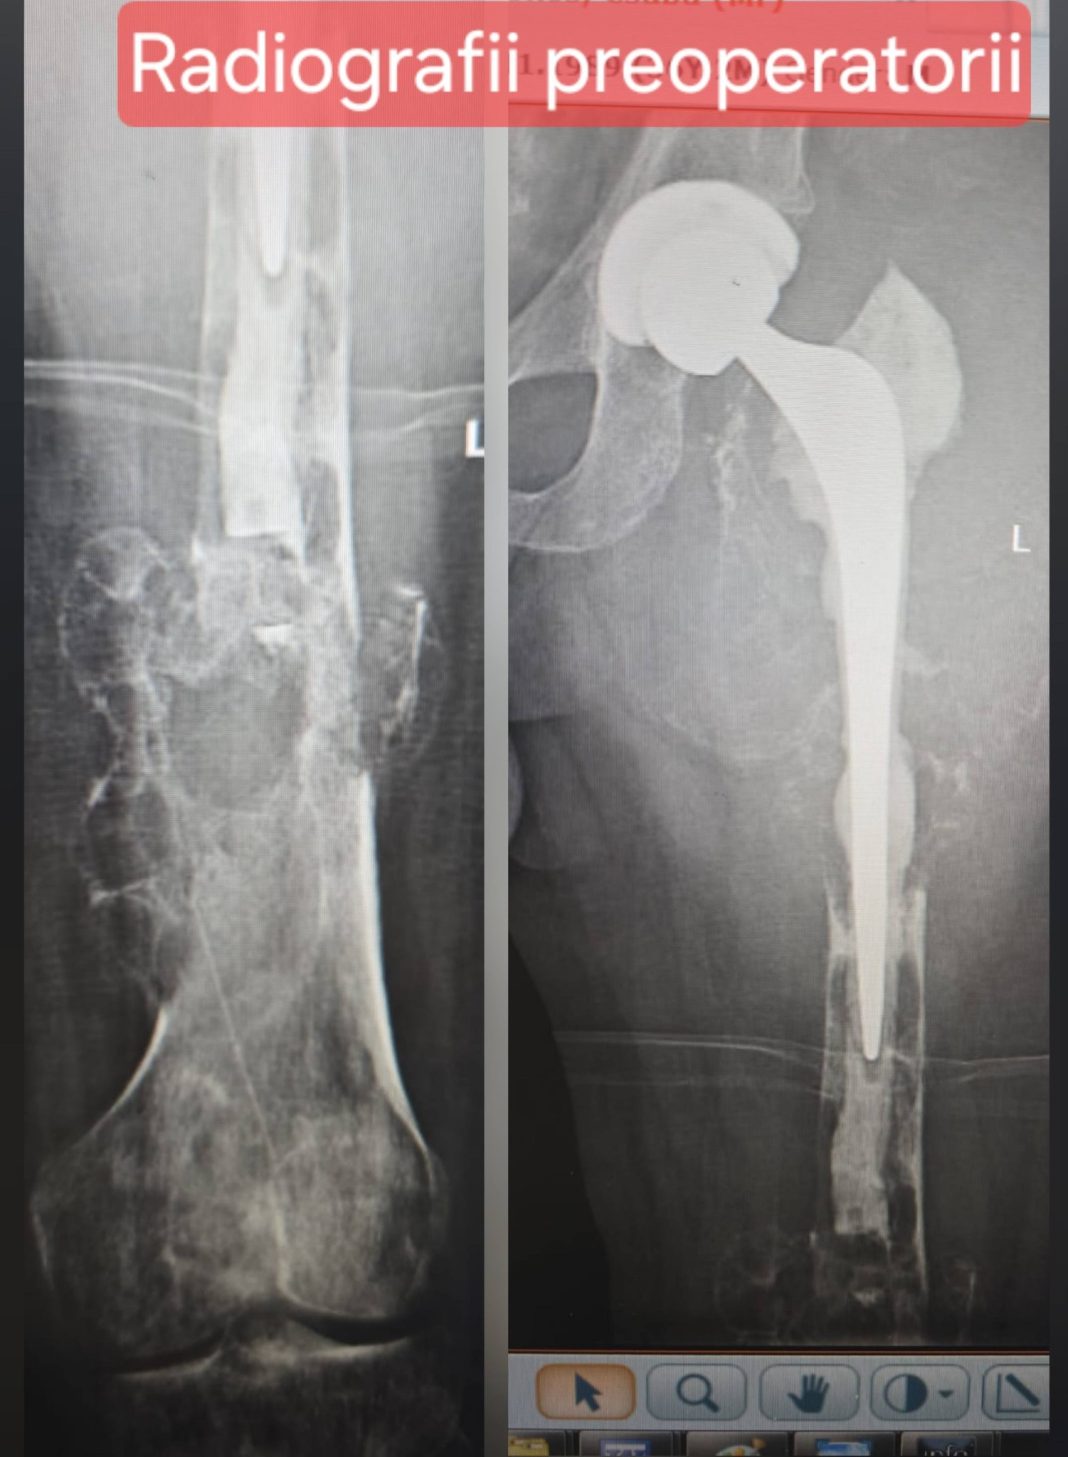

Pacientul, în vârstă de 36 de ani, fusese diagnosticat cu displazie fibroasă femurală acum trei ani și a suferit anterior o fractură pe os patologic, urmată de artroplastie totală a șoldului cu proteză primară. Ulterior, implantul a prezentat decimentare aseptică, iar o biopsie incizională a confirmat prezența unui chist osos anevrismal, ceea ce a condus la transferul pacientului la SUUB pentru tratament specializat.

Pentru a reduce riscul hemoragic, înainte de operație s-a efectuat embolizarea principalelor surse vasculare, realizată de echipa de radiologie intervențională condusă de dr. Bogdan Dorobăț. Intervenția chirurgicală a implicat o echipă multidisciplinară coordonată de Prof. Univ. Dr. Cătălin Cîrstoiu, incluzând medici ortopezi, anesteziști și personal medical auxiliar.